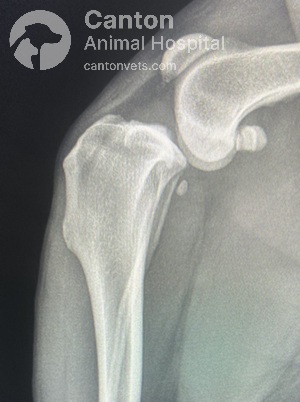

Radiographs (X-rays)

Used to rule out other causes of lameness.

Common findings in chronic or partial CCL tears:

Fat pad compression (“fat pad sign”) and joint capsule swelling due to fluid buildup.

Osteophyte (bone spur) formation on the trochlear ridge, tibial plateau, and patella.

Thickening of the fibrous joint capsule and subchondral sclerosis (increased bone density).

Tibial Plateau Leveling Osteotomy (TPLO) is a precise orthopedic procedure that requires detailed preoperative planning to achieve the best results. Before surgery, radiographs (X-rays) are taken to measure the dog's tibial plateau angle (TPA) and calculate the necessary rotation to achieve an optimal final angle of 5 to 6.5 degrees.